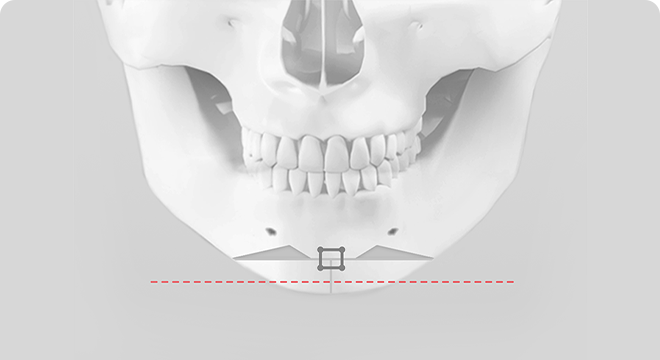

기존의 효과 없는 T절골술

• 턱끝의 모양이 자연스럽지 않으며 튼튼하지 않고 부작용 발생 가능성 높음

기존 T 절골술의 경우 턱끝을 T자 모양으로 절제하고 모아서 고정하는 방법으로 턱끝의 길이와 넓이를 효과적으로 조절할 수 없으며, 턱끝이 넓은 U자 모양이 되거나 울퉁불퉁한 경우가 있습니다. 그리고 절골선이 신경과 치아뿌리에 가까워 수술 후 부작용 발생 가능성이 있습니다.